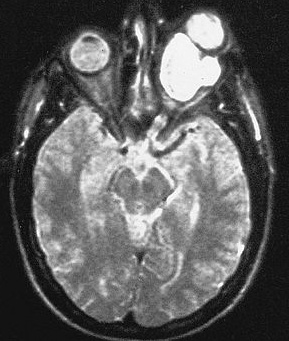

A gadolinium (contrast) enhanced MRI is the diagnostic test of choice for patients with an acoustic neuroma. S100 positive.